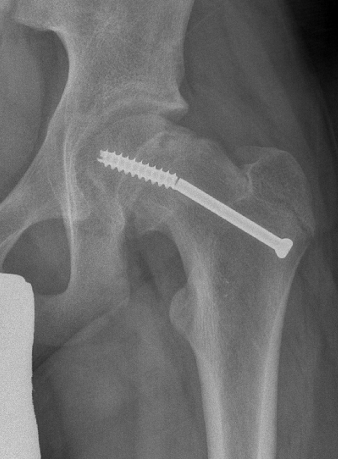

Fixation failure

Cam FAI

Mechanism

Epiphysis heals in a posterior and inferior position with moderate - severe slips

Abnormal contact of relatively anterior neck on the acetabulum